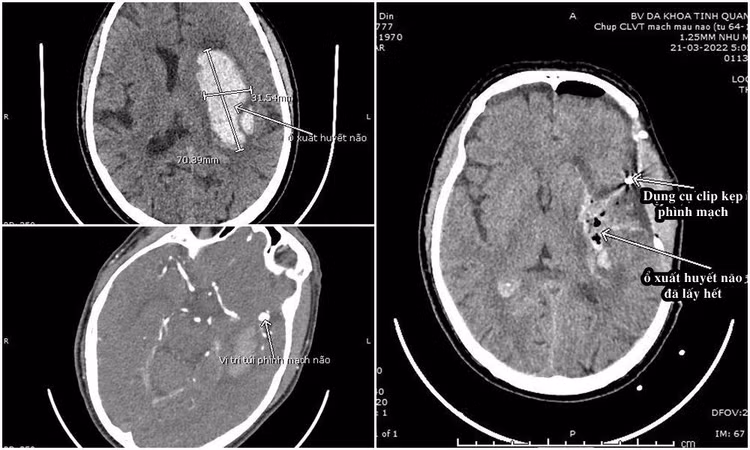

Bệnh nhân vào viện trong tình trạng hôn mê, glasgow 12 điểm, liệt nửa người phải. Kết quả chụp cắt lớp vi tính phát hiện ổ xuất huyết lớn bán cầu trái, kích thước khoảng 70x35mm gây đè đẩy đường giữa 8mm. Đồng thời, phát hiện thêm túi phình động mạch não giữa trái, kích thước 5,6x7,1 mm, cổ túi phình 3,3mm.

Hình ảnh phim chụp của bệnh nhân trước và sau phẫu thuật